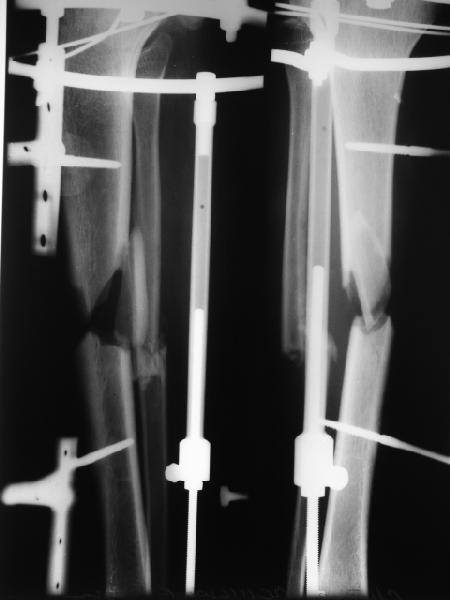

Вот пример, тоже открытый перелом, первичный дефект, пробыл в аппарате 5 мес. Титановый гвоздь, сразу динамический, без покрытия. Больше не делали ничего.

Внедрение одного отломка в другой приведет к укорочению. Резекция с выращиванием резко удлинит срок лечения, вероятно, потребуются еще какие-то операции после завершения дистракции... А самое главное, это избыточные действия. Ведь дефект не сегментарный, краевой контакт есть.

Вполне достаточно закрытого интрамедуллярного остеосинтеза без открытых вмешательств в зоне стыка. Конечно, с рассверливанием. Если есть опасения насчет инфекции, то на гвоздь нанести цемент с ванкомицином.

Гвоздь тут будет эндопротезом диафиза на достаточное время для образования сращения в зоне имеющегося небольшого контакта. И далее страховкой от рефрактур.

При переломах с небольшими краевыми дефектами в большинстве случаев проблему можно решить без особых усилии. Проблема наступает тогда, когда выбирается неадекватный метод фиксации, например применение наружных фиксаторов, где острый “карандаш” костных отломков не создает условия для сращения.

Описано очень много методов восстановления краевых дефектов, и в зависимости от желания дефект можно закрыть открытым или закрытым методом. Из всех предложенных методов предпочтительным является аутопластика из крыла подвздошной кости, но в остром периоде огромный риск осложнений, и желательно с процедурой повременить до безопасного периода. После риминга для восстановления внутриканального кровообращения хватает около 3х недель, а для полного восстановления кровоснабжения конечности надо ждать 6 и более недель.

В лечении переломов с дефектом из методов фиксации, самым популярным является интрамедулярная. Переломы, имеющие более 30% контактной поверхности на гвозде, срастались без дополнительной процедуры. Преимущество гвоздя - это возможность ранней нагрузки, которая создает положительные условия для улучшения трофики мягих тканей. Больные, леченные с ранней нагрузкой в большинстве срастались без необходимости костной пластики.